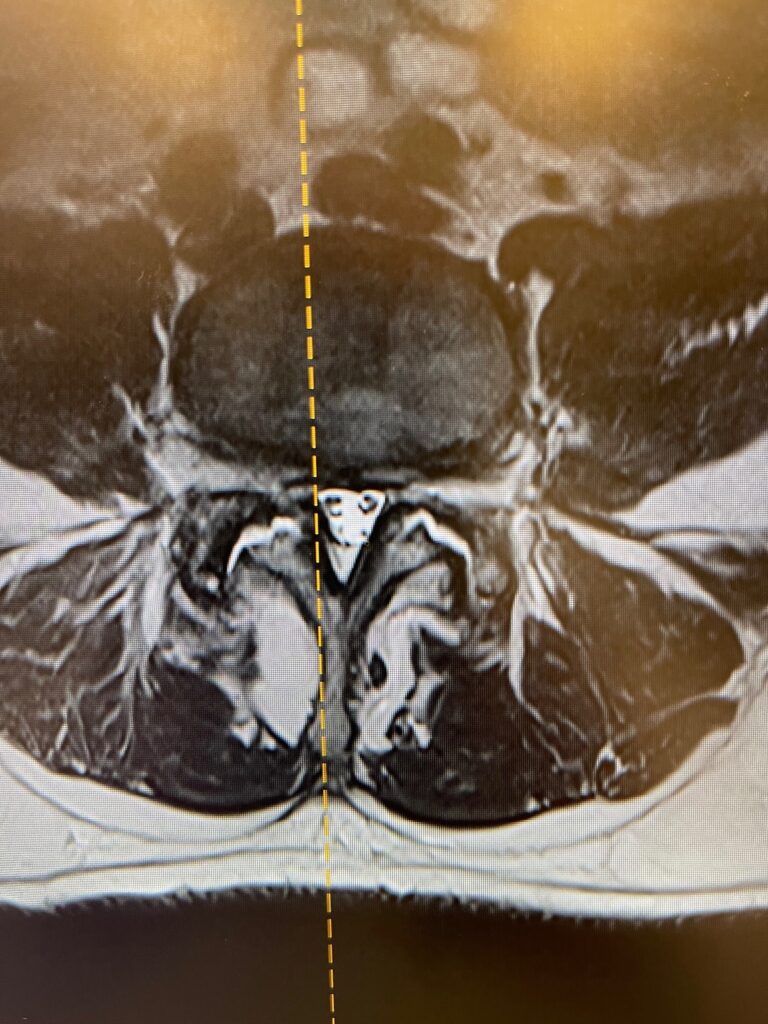

360° Minimally Invasive Fusion for Spondylolisthesis in an Outpatient Setting

This patient underwent a 360° minimally invasive spinal fusion (MISS) to treat spondylolisthesis—performed entirely in an ambulatory surgery center. Traditionally, this type of procedure requires hospitalization and an extended recovery period. However, by leveraging advanced minimally invasive techniques, Dr. Peloza was able to perform the fusion with minimal disruption to tissue and surrounding structures.